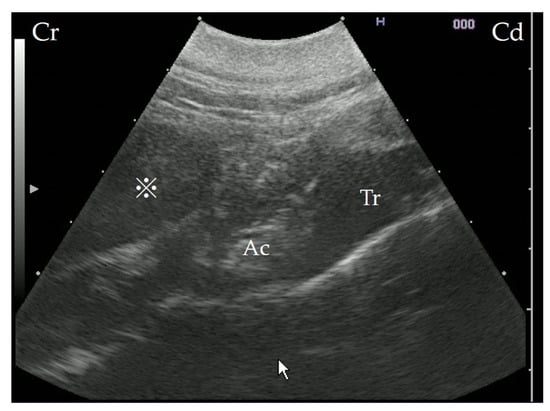

Figure 2. Ultrasonography showing the retropharyngeal mass. The scan was performed from the left side of the cow, with the probe in a transverse position; the trachea and epiglottic cartilage present as landmarks. A mass can be identified on the dorsal surface of the arytenoid cartilage. Cr: cranial; Cd: caudal; Ac: arytenoid cartilage; Tr: trachea area; ※: mass.

3.3. Ultrasonography

Ultrasonography (7.0–8.0 MHz variable linear probe, iViz air, FUJIFILM Healthcare, Tokyo, Japan) was performed without sedation, from the left side of the cow, using the trachea and epiglottic cartilage as landmarks. The interior of the mass was hypoechogenic, though not fluid (Figure 2).